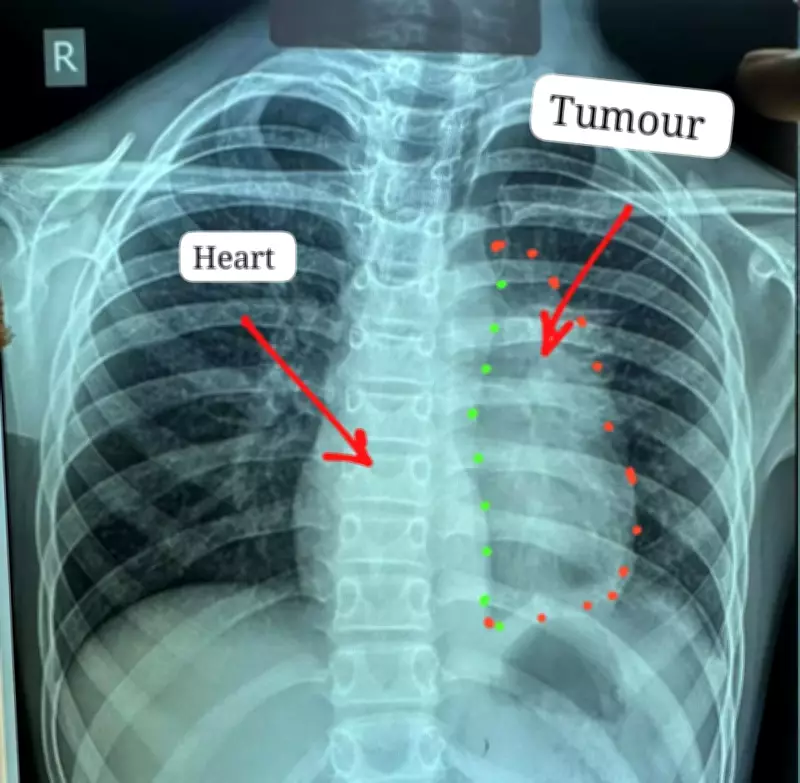

The young patient had been suffering from persistent chest pain, heaviness, and breathlessness for about six months before diagnosis. Medical investigations revealed a substantial tumor in his chest cavity that was tightly adherent to critical structures including the heart and major blood vessels. After several hospitals reportedly declined to operate due to the extreme risks involved, the boy was referred to Ambedkar Hospital for specialized care.

The tumor presented extraordinary surgical challenges due to its extensive involvement with multiple vital organs. According to the medical team, the cancer had spread to involve the heart, pericardium, phrenic nerve, aorta, main pulmonary artery, left atrium, and part of the lung. Such cases are considered among the most difficult in thoracic oncology, with complete tumor removal often deemed nearly impossible.

The tumor was later identified as invasive thymic carcinoma, specifically type-B thymoma at stage 3. This cancer typically affects individuals between 40 and 60 years of age and is exceptionally rare in pediatric patients. To address this complex case, surgeons employed a dual-approach technique combining both sternotomy and thoracotomy procedures.

This involved making incisions through both the breastbone and chest wall to access the tumor, which measured approximately 12x8 centimeters and weighed nearly 400 grams. The four-hour procedure was conducted with a heart-lung machine kept on standby for potential emergencies, highlighting the meticulous preparation undertaken by the surgical team.